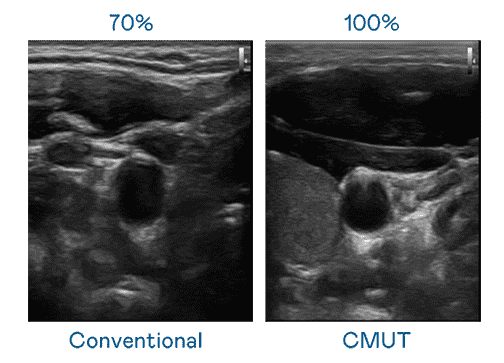

CMUT 技术是一种用电容式微机电元件来产生超音波讯号的技术。。。。与传统 PZT 压电式技术相比,,CMUT 频宽增加 30%,,,更宽频的超音波讯号让影像解析度大幅提升,,,,是实现高影像品质医疗超音波扫描、、促进精准医疗发展的关键技术。。。。

大频宽带来超清晰影像

超音波影像的解析度高低,,首先取决于探头能发出的讯号频宽。。。。尊龙z6 CMUT 可提供高清晰的超音波讯号,,提供高频宽、、、高灵敏度、、影像纹理细节更高的超音波影像,,协助医护人员缩短影像判读时间及利用精准的医疗影像进行诊断。。。